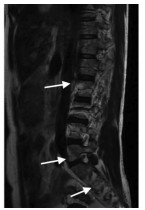

Diagnosis and management of primary biliary cholangitis with osteoporosis

Wen ZHANG, Shuyan CHEN, Tingting LYU, Hong YOU

2021, 37(10): 2272-2276. DOI: 10.3969/j.issn.1001-5256.2021.10.004

Abstract(1174) HTML (345) PDF (1899KB)(165)

Abstract:

Primary biliary cholangitis (PBC) is a chronic progressive cholestatic liver disease often observed in the middle-aged and elderly women and it can eventually lead to liver cirrhosis or liver failure. Osteoporosis is one of the common complications in PBC patients and is characterized by decreased bone mass and increased susceptibility to fractures. Osteoporosis and fractures caused by osteoporosis seriously affect the quality of life of PBC patients, and with the improvement of PBC treatment strategies and the increase in life expectancy, early diagnosis, prevention, and treatment of PBC with osteoporosis is of particular importance. This article briefly summarizes the epidemiology, pathogenesis, and diagnosis and treatment of patients with PBC and osteoporosis and proposes current challenges and future research directions.